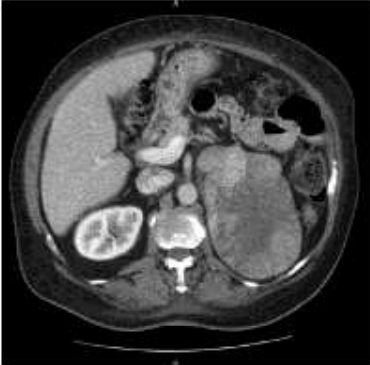

Menino de 1 ano e 3 meses, procura pediatra devido a aumento do tamanho peniano, pilificação escrotal e acne em face. A colega solicita uma RM Crânio que não evidencia alterações e TC abdome com a seguinte imagem:

Sobre a sua hipótese diagnóstica, é incorreto afirmar: